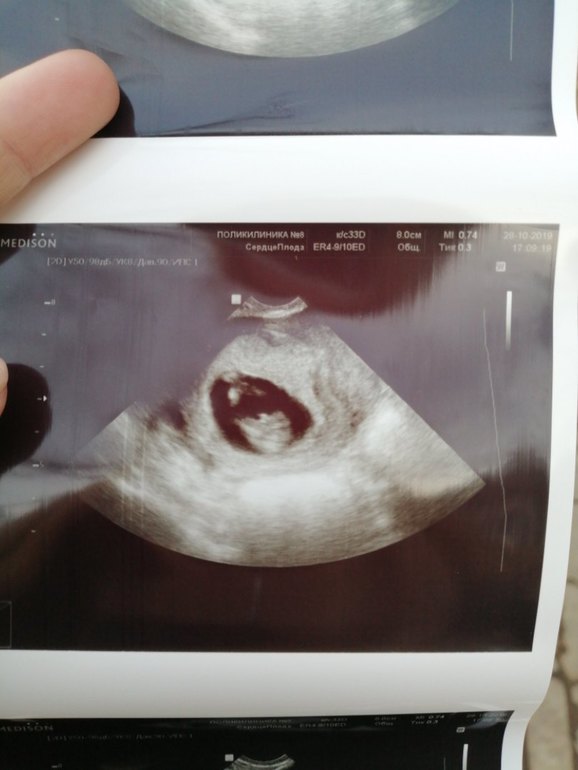

А вот и мы

А на счёт малыша я на узи пошла чсс у него 177 было Ручки в кулочки зажал и не двигается, узист говорит как зайчик замер а сердце колотится, я выдохнул чсс 166 потом смотрю ножкой пинать начал)